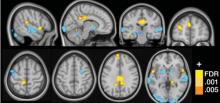

Actualité publiée il y a 9 années 6 moisFIBROMYALGIE: On a trouvé sa signature neurophysiologique !